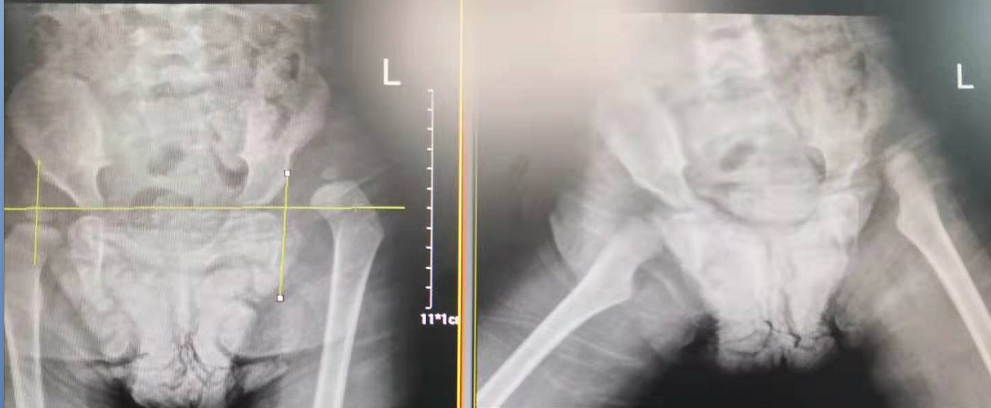

術(shù)前

術(shù)后

2歲零1個月的幼兒玥玥(化名)因先天性髖關(guān)節(jié)脫位(也就是我們常說的“長短腿”)來到了瀘州市中醫(yī)院治療。在醫(yī)院骨傷三科岐黃名中醫(yī)、副主任中醫(yī)師鄭磊的帶領(lǐng)下,科室與麻醉科密切配合,順利為玥玥實施了手術(shù)。